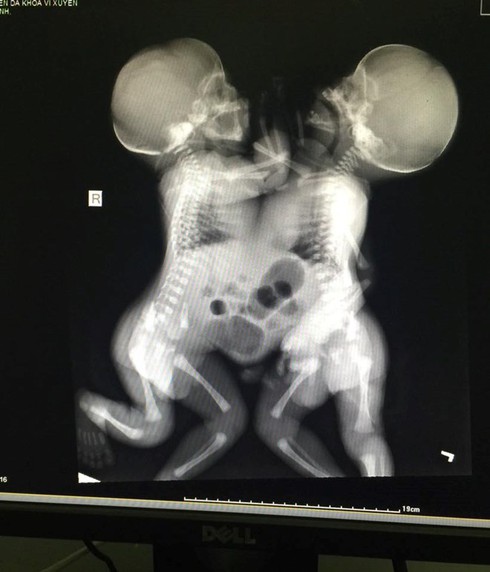

Đến đêm 13/7, vợ anh đau bụng, vỡ ối nên anh đưa vợ đến Bệnh viện huyện đẻ. Khi bác sĩ bất ngờ thông báo hai bé dính nhau, anh cũng chưa hiểu là dính như thế nào. Khi nhìn thấy con, lúc đó anh mới thấy run và lo sợ sẽ không giữ được con.

Bản thân ông Chài cũng chỉ biết xuống với cháu. Nhìn cháu từ ngoài cửa kính phòng hồi sức tích cực. Ông rất lo khi bác sĩ trao đổi với ông về tình trạng của hai bé hiện nay khó phẫu thuật bởi hai bé chung gan và dính tim.